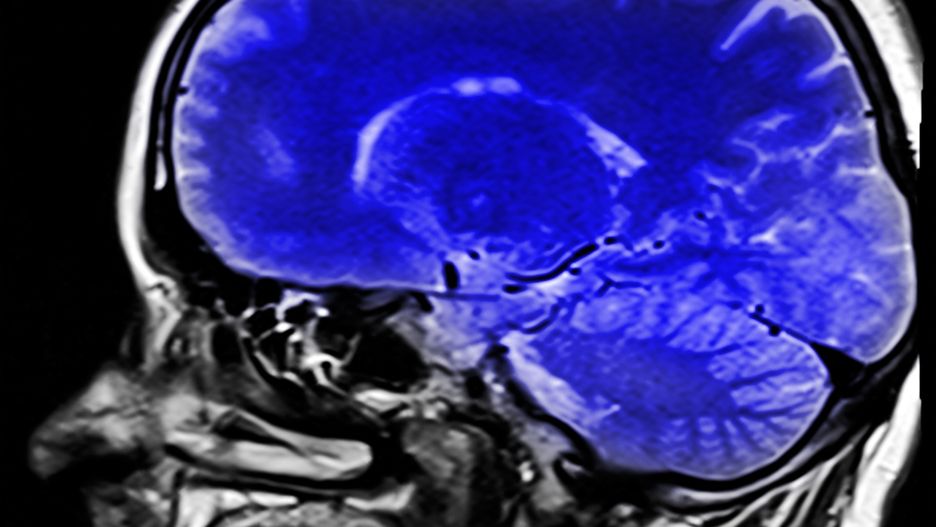

Najnowsze badania wykazały, że drobne cząsteczki zanieczyszczeń mogą dostać się do mózgu. Podejrzewane o toksyczność cząstki tlenku żelaza mogą być odpowiedzialne za rozwój takich chorób jak Alzheimer. Naukowcy nazwali to odkrycie "wstrząsającym".

Badania wpływu zanieczyszczeń powietrza skupiały się do tej pory na płucach i sercu. Okazuje się jednak, że uwaga naukowców powinna zwrócić się również w stronę mózgu. Badania przeprowadzone na angielskim Lancaster University wykazały, że w tkance mózgowej osiadają miliardy cząsteczek związku znanego jako magnetyt. Podnosi to całą masę pytań na temat zdrowotnych konsekwencji zanieczyszczenia.

To szokujące. Badając tkankę mózgową, widzieliśmy cząsteczki w komórkach. Kiedy wydobyliśmy je za pomocą magnesu, okazało się, że są ich miliony w jednym gramie tkanki. To miliony okazji, żeby dokonać uszkodzeń - stwierdziła prof. Barbara Maher, prowadząca badania, cytowana przez BBC.

Konsekwencje tego odkrycia mogą być poważne. Według prof. Davida Allsopa, specjalisty od Alzheimera i innych chorób zwyrodnieniowych układu nerwowego, cząsteczki znalezione w mózgu mogą być istotnym czynnikiem w procesie rozwoju tych schorzeń. Badania będą kontynuowane.